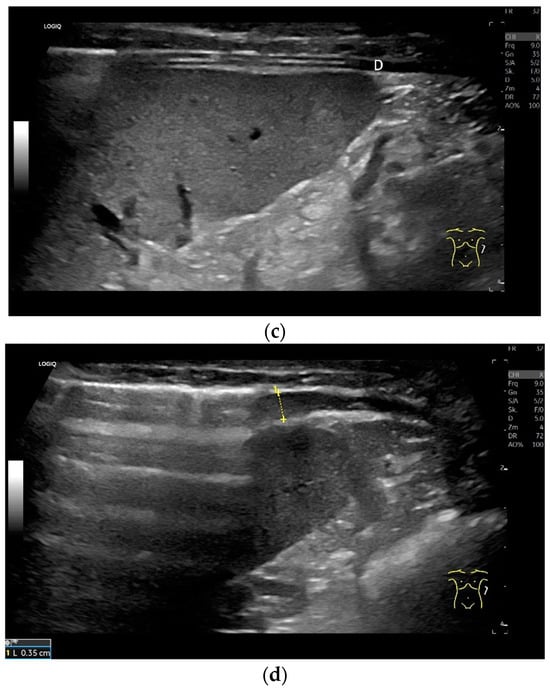

Subcostal transducer position: An abdominal sector or cardiac transducer (2–5 MHz) is used in the subcostal window. This position is used to assess diaphragmatic excursion. The transducer is placed between the linea medioclavicularis and linea axillaris anterior. The diaphragmatic excursion can then be visualized and measured in M-mode (Figure 5). The gallbladder and inferior vena cava are important landmarks. It is important to guide the ultrasound probe as perpendicularly as possible. The M-mode axis should meet the diaphragm at an angle of 90%. In this position, diaphragm thickness in inspiration and expiration can also be measured using M-mode, and diaphragm shortening can be calculated. However, in normal adults, the diaphragm can usually only be visualized in this position using abdominal sector transducers and is less accurately delineated than with a linear transducer from the lateral side in the anterior axillary line.

Diaphragmatic excursion and amplitude reflect the range of mobility and contraction. They can be assessed using different breathing maneuvers: during quiet breathing, with deep inspiration and during sniffing. A sniff maneuver is a short, forced inspiration. The movement of the diaphragm is ideally mapped in M-mode. The amplitude of diaphragmatic movement can then be measured on the M-mode curve, as can the speed of the diaphragm excursion. Standard values in numerous studies for diaphragm thickness, contraction and movement amplitude depending on body position, gender and diaphragm side are listed in Table 1 and Table 2. In addition to mean values and standard deviations, various studies also report the lower limit of normality of diaphragm thickness and contraction as well as the derived parameters. These are limit values that indicate how high a parameter must be in order not to be considered pathological. In this way, patients with dysfunction can be identified. There is also information on the upper limit of normality. However, the meaning of such a value is not entirely clear.